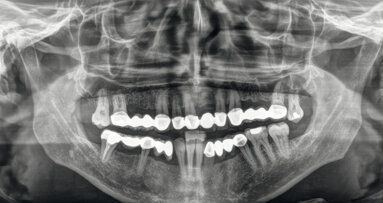

La necessità di poter effettuare un prelievo venoso per la tecnica di rigenerazione ossea è solo una delle esigenze del laureato in odontoiatria. Se tecnicamente può imparare ad effettuare un prelievo, legalmente la sua laurea gli consente di effettuarlo?

Il dibattito è da tempo aperto ed i pareri non sono sempre stati univoci. Ora la FNOMCeO, sollecitata da più Ordini provinciali, si esprime sulla possibilità per il laureato in odontoiatria e protesi dentaria di eseguire dei prelievi venosi. La normativa di riferimento, ricorda il presidente Roberta Chersevani nella nota inviata a tutti i presidenti OMCeO e CAO, è quella contenuta nel Decreto del Ministero della Salute del 2 novembre 2015 “Disposizioni relative ai requisiti di qualità e sicurezza di sangue e degli emocomponenti". Nello specifico, ricorda il presidente FNOMCeO, nell'allegato 10 del predetto decreto concernente "Emocomponenti per uso non trasfusionale" al punto 3 si sancisce: «Per le attività che riguardano gli emocomponenti per uso non trasfusionale, si applicano le seguenti modalità: la richiesta deve essere effettuata da un medico o, solo per le attività cliniche di competenza, da un odontoiatra».

Viene poi stabilito, continua la nota FNOMCeO, che «l'applicazione di emocomponenti in ambito odontoiatrico può essere effettuata da un odontoiatra solo per le attività cliniche di competenza». Si può quindi affermare, conclude il presidente Chersevani, «che il sanitario iscritto al solo Albo degli odontoiatri può svolgere questa prestazione clinica solo per le attività di competenza della professione odontoiatrica». Nota che non solo chiarisce gli ambiti di intervento del laureato in odontoiatria, ma sembrerebbe limitare al laureato in medicina iscritto al solo Albo degli odontoiatri la possibilità di effettuare un prelievo venoso solo se finalizzato alla cura odontoiatrica, a differenza del collega iscritto anche all'Albo dei medici.